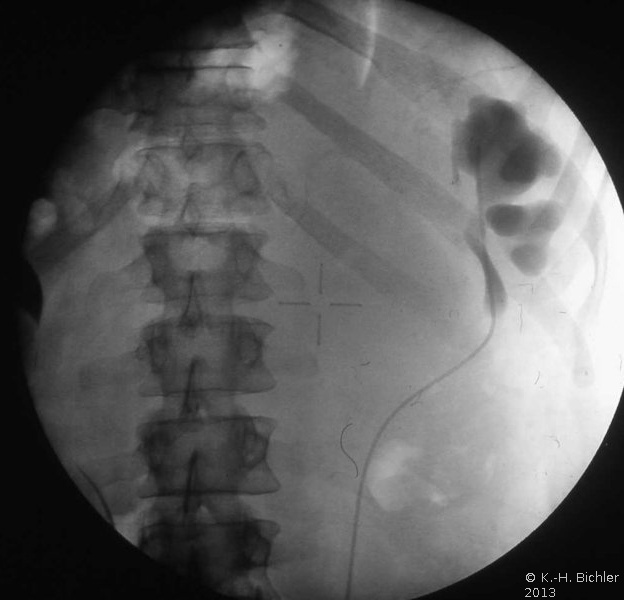

Die Röntgenübersicht der Niere und ableitenden Harnwege zeigten keinen Anhalt für Konkrement. Im Ausscheidungsurogramm eine "stumme Niere" links (Abbildung 19a). Bei der retrograden Sondierung links fand sich keine Abflussbehinderung (Stein oder Stenose) (Abbildung 19c). Im MCU kein Anhalt für Reflux (Abbildung 19b). Im Nierenfunktionsszintigramm MAG3 wurde eine seitengetrennte Funktionsverteilung von rechts zu links wie 93% zu 7% festgestellt. Zur Abklärung eventueller Gefäßalterationen erfolgte eine Renovasographie mit dem Nachweis einer langstreckigen Stenose der linken Arteria renalis (Abbildung 19d). Wegen des Verdachtes auf eine generalisierte Arteriitis wurden Angiographien weiterer Gefäßgebiete durchgeführt: Dabei fanden sich eine geringgradige Einengung der infrarenalen Aorta und der linken Arteria subclavia.